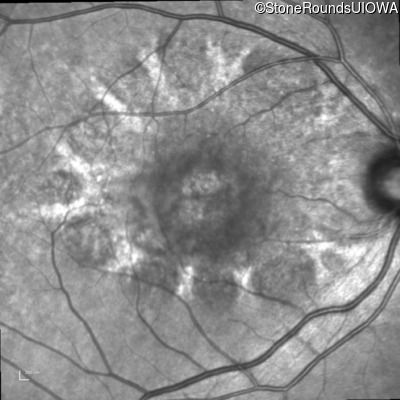

Best Disease (IIB)

Age at visit: 49 years

This 49 year old man first experienced some mild metamorphopsia at age 35.